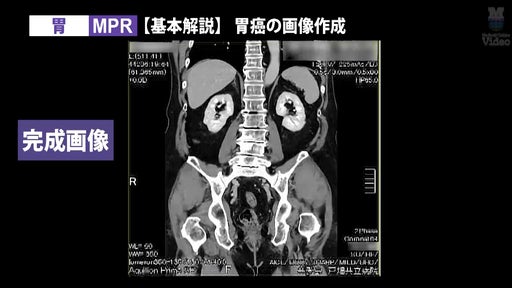

さらに今回は、人気の「3D画像作成(CT)」シリーズに胸郭出口症候群(TOS)・胃をテーマにした新作を追加。加えて、現場で注目度の高い「医療機関におけるパワーハラスメント問題」「児童虐待への対応」を扱う医療法律相談シリーズも新たに公開しました。

3D画像作成の人気シリーズに、「胸郭出口症候群(TOS)」と「胃」の新作を追加。CT撮影から3D画像作成までの流れを、実際の画面キャプチャを交えて徹底解説します。

監修:山本晃義先生(戸畑共立病院)/実演・解説:田原琢朗先生

3D画像作成技術をさらに磨きたい放射線技師に向けた、実践的な内容です。